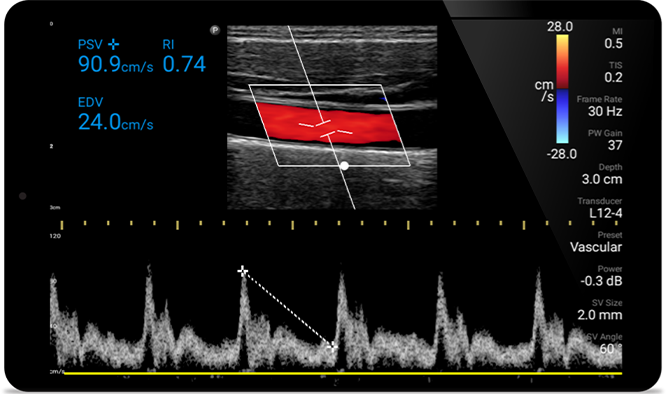

Early detection can help keep conditions from becoming critical

Congestive heart failure is a growing issue today. Discovering it earlier with in-office ultrasound can greatly improve survival rates.